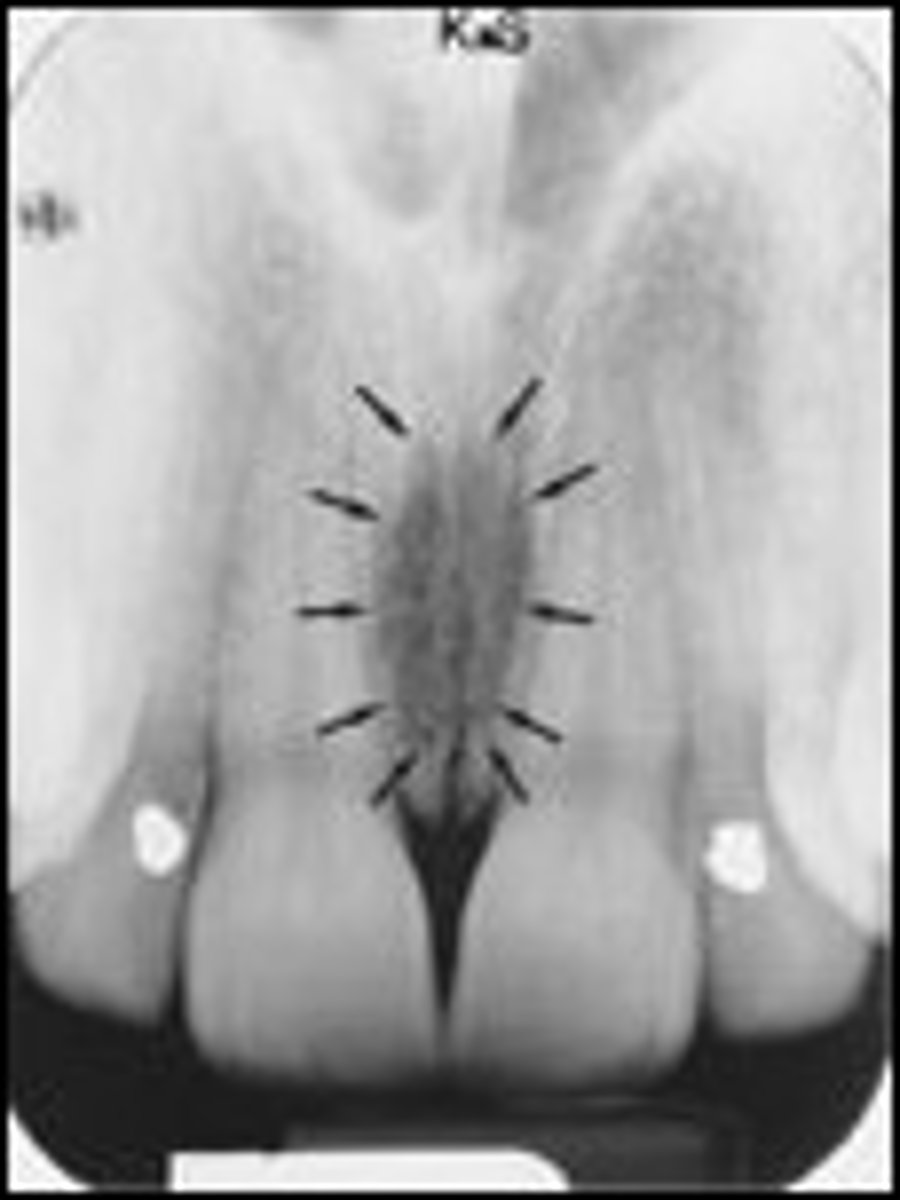

Incisive foramen

What is the radiolucent structure seen here?